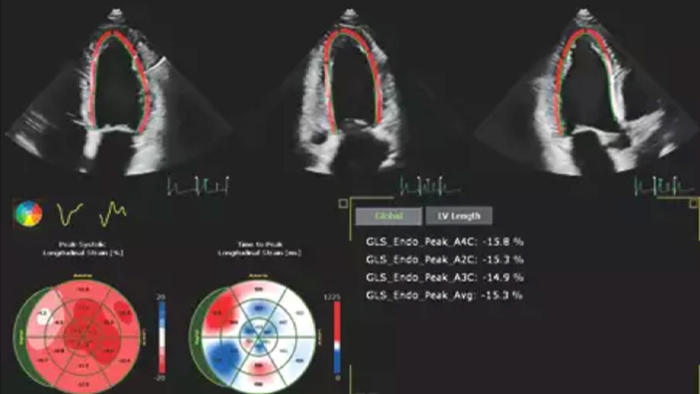

Robust and reproducible imaging tools are important to diagnose and monitor disease progression in heart failure. Current guidelines support the use of advanced echocardiography tools such as longitudinal strain and 3D assessment of LV and RV volumes and function.

Automation for robust, proven reproducible cardiac quantification in both 2D and 3D.

Echo is often the first cardiac imaging test that’s performed for patients with suspected heart failure. An echocardiogram gives us a wealth of information on cardiac structure and function using both 2D and 3D tools. Echocardiography can help us understand the etiology of heart failure in many situations. I routinely use information derived from both 2D and 3D analysis and strain to better understand my patients. AutoStrain, Dynamic HeartModel and Auto RV are invaluable tools that are used both in the diagnosis and surveillance of patients with heart failure.”